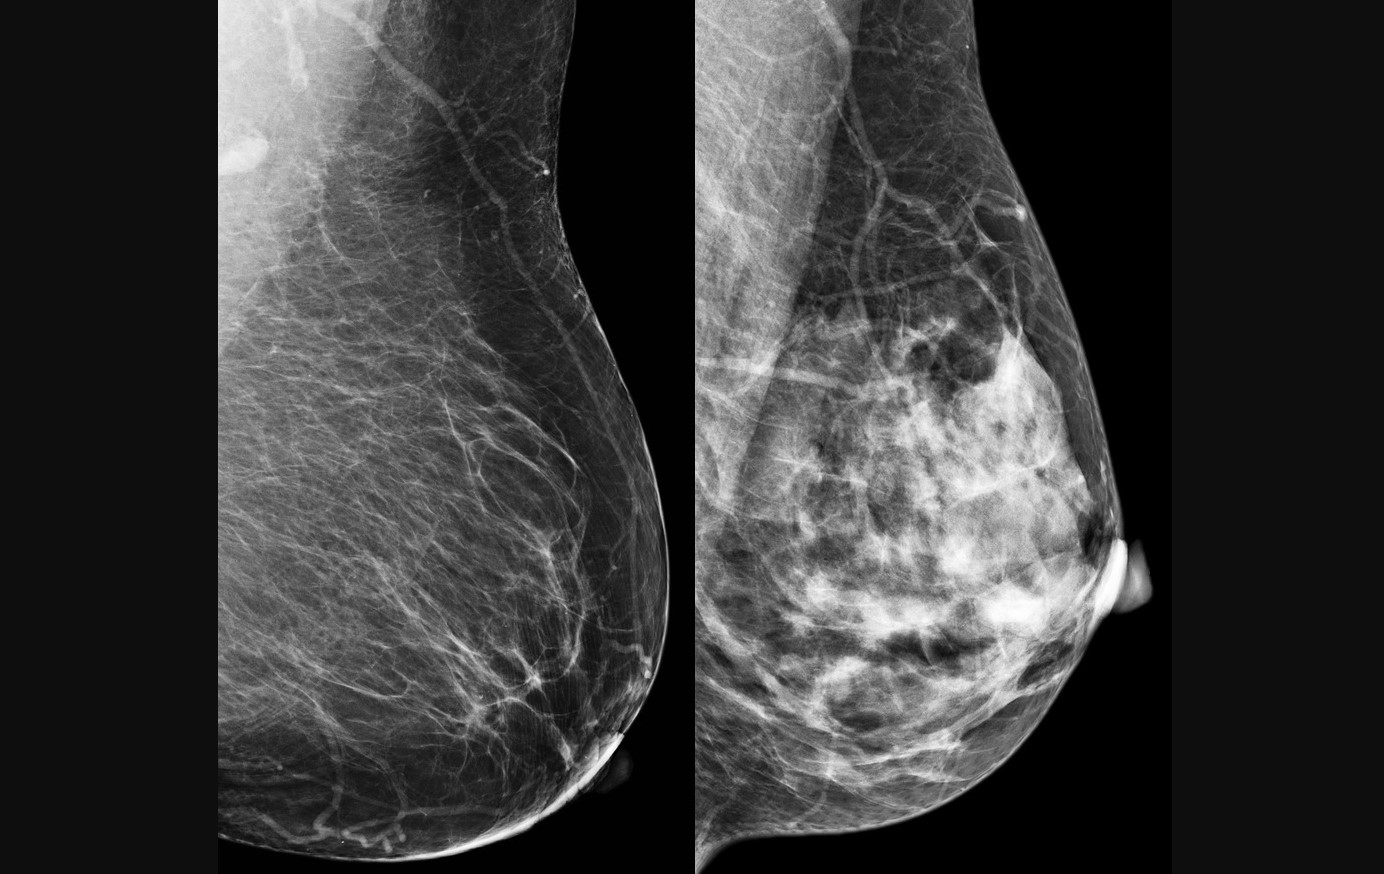

Breast cancer is the leading cause of cancer death in women (image: CDC)

Among breast cancer cases, tumors may have different levels of HER2 protein expression. Some have high levels and are classified as HER2-positive, indicating eligibility for specific targeted therapies. Others with lower or absent expression are called HER2-low or HER2-zero, respectively. These tumors belong to the HER2-negative group, though some newer treatments, such as antibody-drug conjugates, have also shown benefit in these cases.

For HER2-positive tumors, the standard treatment is a combination of chemotherapy and antibodies that block the growth signals of the protein. This therapy costs an average of BRL 40,000 (approximately USD 7,500.00) per patient and can cause side effects such as nausea, diarrhea, and a drop in white blood cell count.

The National Cancer Institute (INCA) notes that breast cancer is one of the most prevalent cancers among Brazilian women (excluding non-melanoma skin cancer) and the leading cause of cancer-related death among women. The estimated figures for total breast cancer diagnoses in 2025 point to 73,000 new cases, with the Southeast being the region with the highest incidence, according to the publication Breast Cancer Control in Brazil: Data and Figures 2025, which was released to mark Pink October, a month dedicated to raising awareness and fighting the disease.